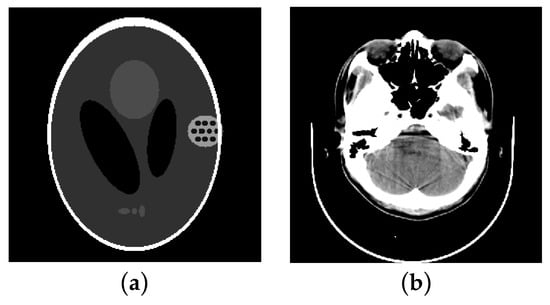

3.1. Numerical Phantom Experiments

3.2. Head Phantom Experiments